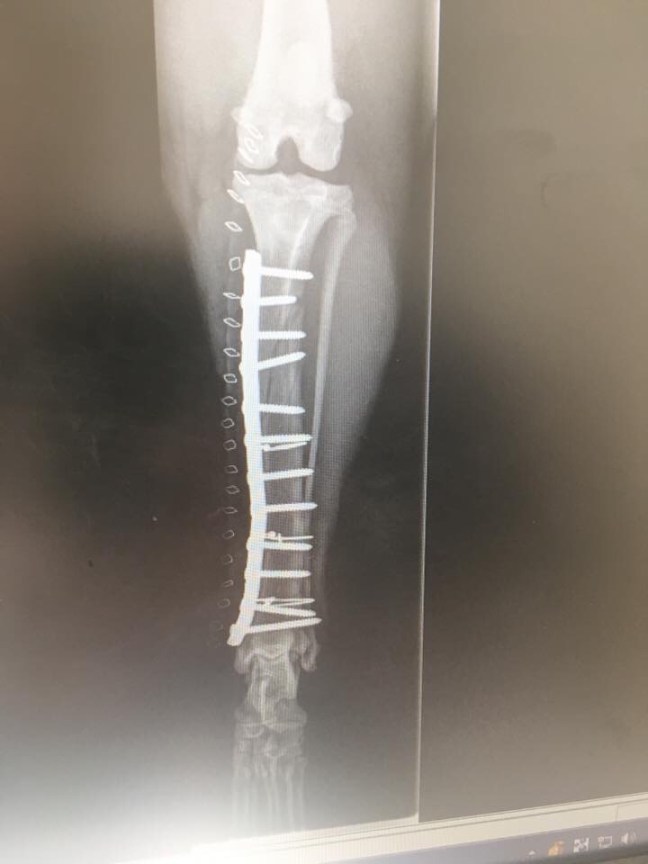

The break was a doozy- a spiral fracture the entire length of the tibia, missing the ankle by a mere millimeter. The surgeon implanted a plate, held with twelve screws.